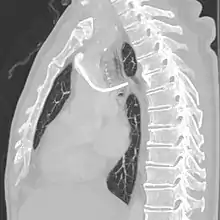

After the entry site is punctured with ultrasound, a guidewire is inserted with the tip of the guidewire reaching the inferior vena cava. The proximal end of the guidewire is secured to prevent dislodgement. Then a chemoport pocket is created on the deltopectoral region at 2.5 cm below the level of clavicle by using a scalpel. Bupivacaine with adrenaline (0.25%) is used as local anesthetic to reduce the formation of haematoma and prolong the anesthetic effect. After the pocket is created, a trocar is used insert a silicone catheter from the pocket towards the internal jugular vein puncture site. A peel-away sheath is then inserted to facilitate the insertion of the silicone catheter into the cavoatrial junction. Silicone catether insertion should be done during breath hold at inspiration. The peel-away sheath should be pinched to prevent air embolism. The proximal end of the catheter is connected to the port within the skin pocket later after irrigation of the pocket with normal saline.[3]

The port is then sutured on two sites to the underlying muscles. The tip of the catheter is checked for kinks and position using a fluoroscope. Besides that, aspiration of blood and contrast injection through the chemoport can also be used to confirm the position. The port is the closed in two layers (subcutaneous tissue is sutured first, followed by the skin). Sterile dressing is then placed on the port.[3] The optimum site to park the tip of the catheter is at the cavo-atrial junction or with margin of error of not more than 4 cm above the junction.[3]

The port access site is fixed at 5 cm below the midline of the clavicle and 9 to 10 cm lateral to the midline of the chest. Then, a 5 to 6 cm incision is made to create a subcutaneous tissue pouch for the placement of port access site. A tunnel is made from the port access site until adjacent to the internal jugular neck wound. A port catheter is passed through the tunnel where one end is attached to the chemport and another end is left hanging out near the IJV insertion site. The length of the hanging port catheter should be about 16 to 17 cm (or can be measured from the IJV insertion site until 2 cm below the sternal angle where the right atrium should begin). This portion of the port catheter should later be inserted through the IJV insertion site until it reaches the aortocaval junction. The IJV insertion is dilated using a plastic dilator. Peel-off sheath was then inserted over the guidewire. Blood is aspirated from the catheter to confirm the position. Then, the free-end of the port catheter is inserted through the peel-off sheath. After the tip of the port catheter is confirmed at the aortocaval junction, the peel-off sheath is taken-off by peeling away with two hands. While peeling off, the port catheter should remain in-situ. Stitches are only removed after 14 days post operation.[5]